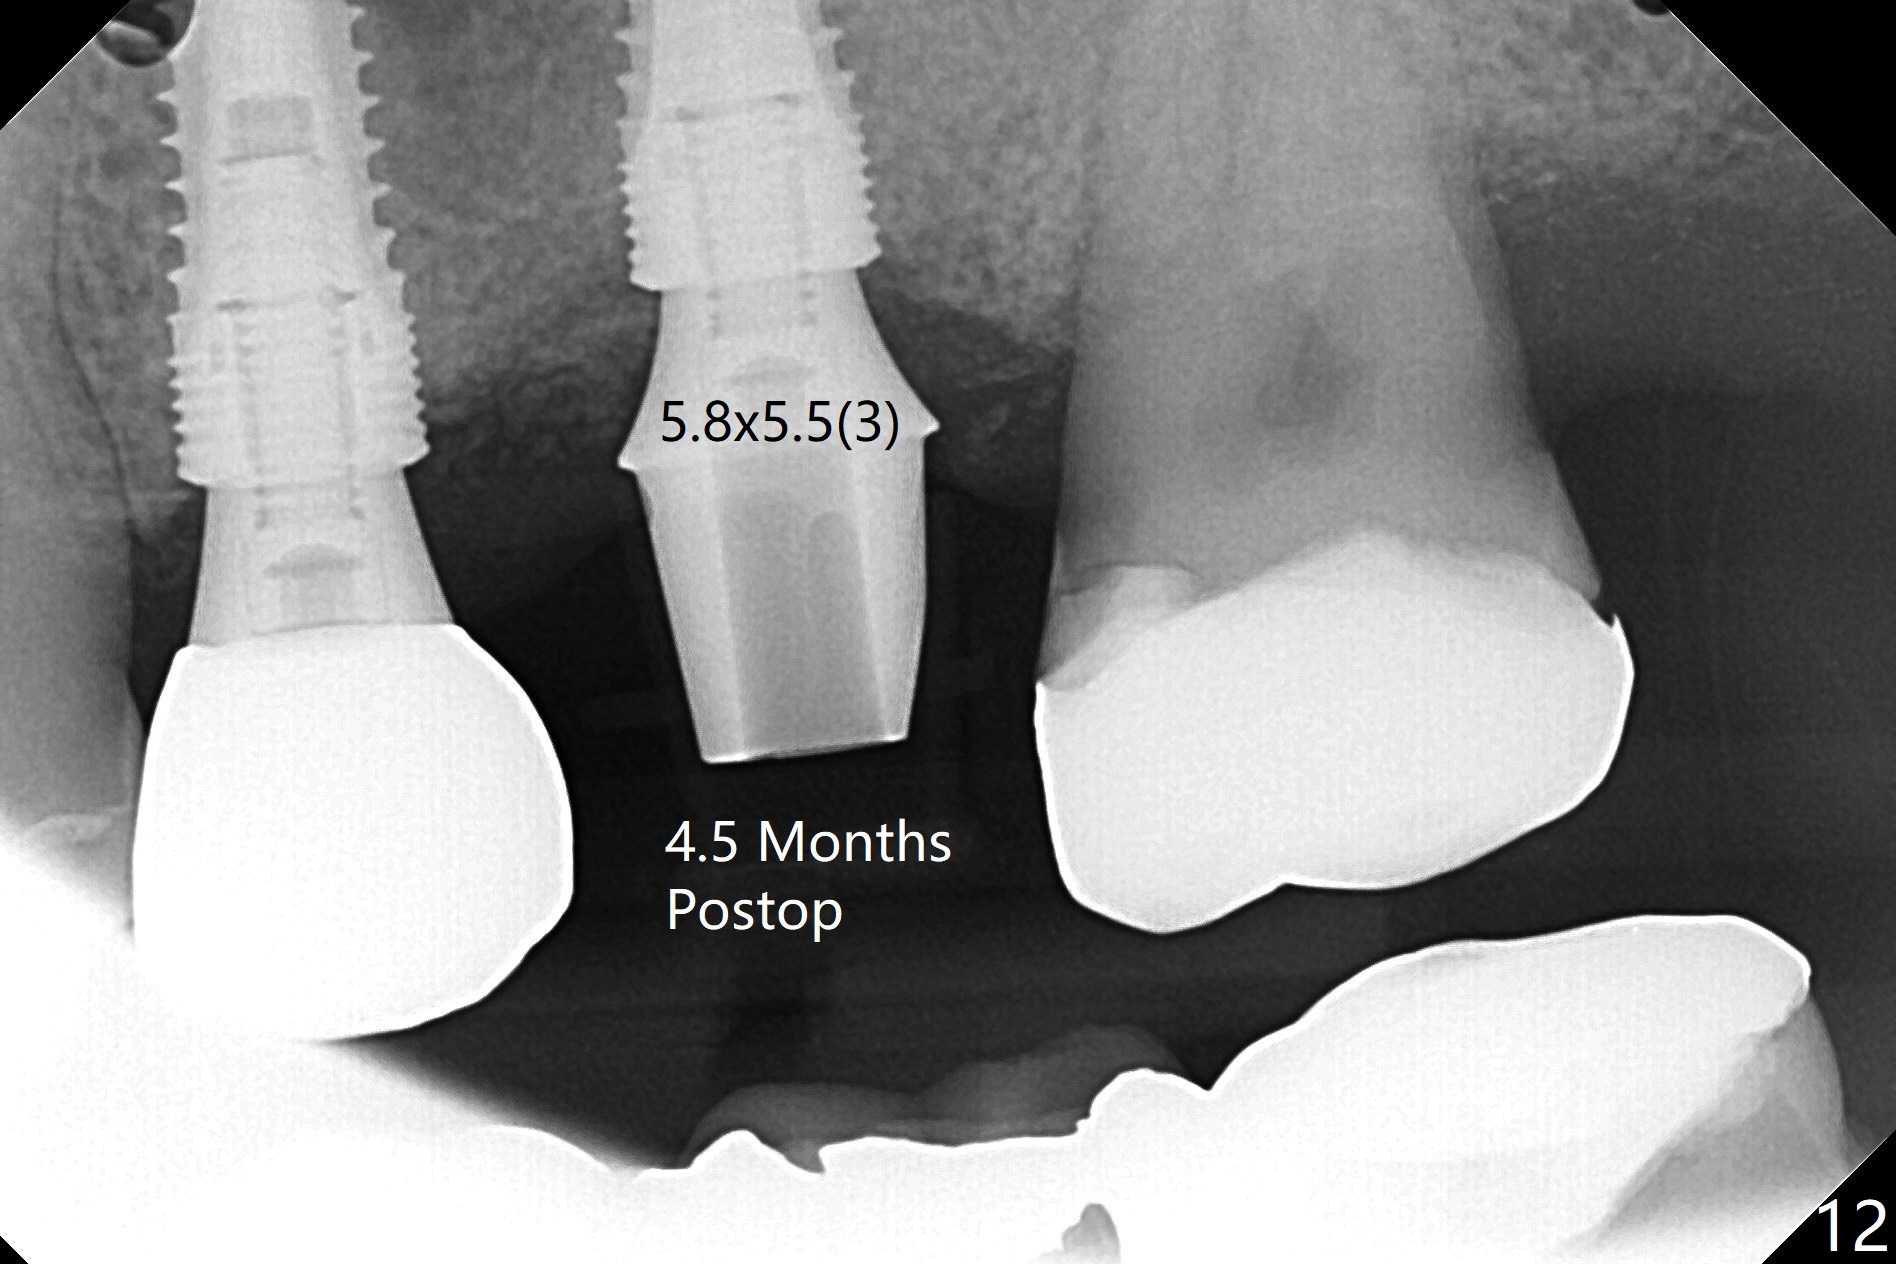

60岁男,左上6(牙根折裂严重骨质吸收)位点保存后6个月,回来植牙。术前CT显示骨质密度低,宽度足够,角化龈也宽,前后牙齿都有牙冠,制作导板麻烦,所以采纳徒手种植。使用4毫米活检打孔刀(Biopsy Punch)进入,简化手术,但是又怕开口不正,不敢用大号植体,术后CT发现钻洞偏颊侧。针对骨质密度低,使用1.2毫米钻头后(约8毫米),使用旋转式骨扩张器直至2.4/3.7毫米(图一(红虚线:原来骨质缺损)逐渐增加深度至11毫米),备洞几乎没有失去骨质,钻洞周围骨质密度谅必增高),取出最后一个扩大器后发现上颌窦底板破裂,放置粘性骨粉,使用4毫米报废植体做上颌窦提升,重复一次(图二,三),稳定性尚可。再次放置骨粉和PRF膜,使用正式植体提升(4.5x8毫米),临床上很难判断是否植体植入牙槽嵴之下(可能骨质疏松),只好拍摄CT(图四,五),好像正好牙槽嵴下,不过又植入骨粉一些(图七:*)。植体扭力~15Ncm,保险起见,放置愈合帽,表面放置少许骨粉以及打孔留下的牙龈(图六:G,之前一直泡在PRF上清液里),牙周胶水固定游离牙龈以及牙周敷料保护。术后6小时没有鼻出血。所以骨质缺损严重,植骨后,虽然缺损外形得到恢复,但是骨头质量,固定植体能力还不够。植牙时,需要适当改变手段,例如使用骨凿,提高骨质密度,而不是单纯使用钻头。术后病人恢复正常,没有疼痛,六天复诊,牙周敷料已经脱落,打孔的牙龈附着颊侧,部分骨粉暴露,但是看样子挺稳定,好像游离牙龈必须缝合。使用树脂敷料牢靠些。术后五周,伤口基本愈合,一处未愈合,与下面骨粉相通,用牙周探针稍微搅动,出血(图九)。擦干血迹,伤口还不错(图十)。术后2个月伤口好像正常愈合(图十一)。术后4.5个月根尖片显示6种植比5深,往后螺纹暴露可能性减少(图十二)。